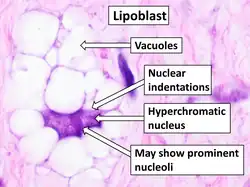

Lipoblast

A lipoblast is a precursor cell for an adipocyte.[1] Alternate terms include adipoblast[2] and preadipocyte.[3] Early stages are almost indistinguishable from fibroblasts.[4]

Lipoblasts are seen in liposarcoma[7] and characteristically have abundant multivacuolated clear cytoplasm and a dark staining (hyperchromatic), indented nucleus.